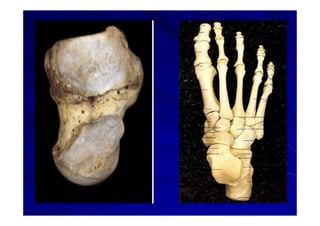

El documento presenta una introducción a la anatomía normal. Explica que la anatomía es el estudio de la estructura del cuerpo humano y clasifica los tipos de anatomía. Además, enumera los contenidos que serán cubiertos en el curso, incluyendo conceptos, posición anatómica, vocabulario, osteología, artrología y miología.